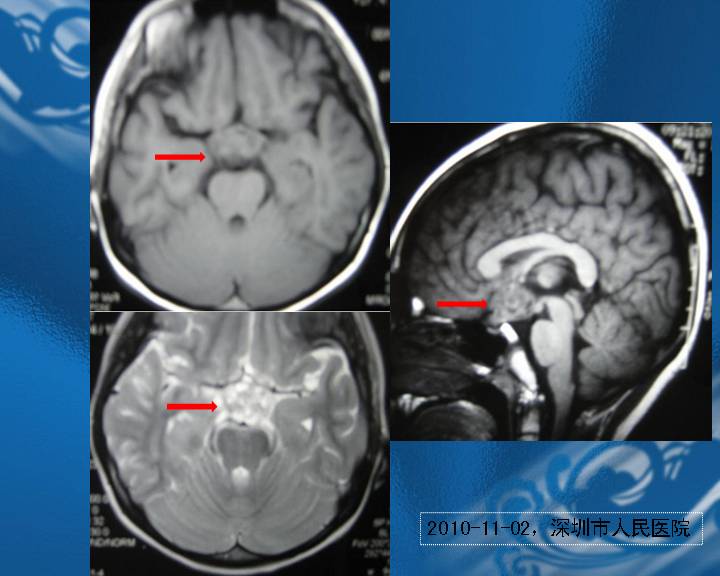

范珂:颅内生殖细胞瘤的神经眼科表现